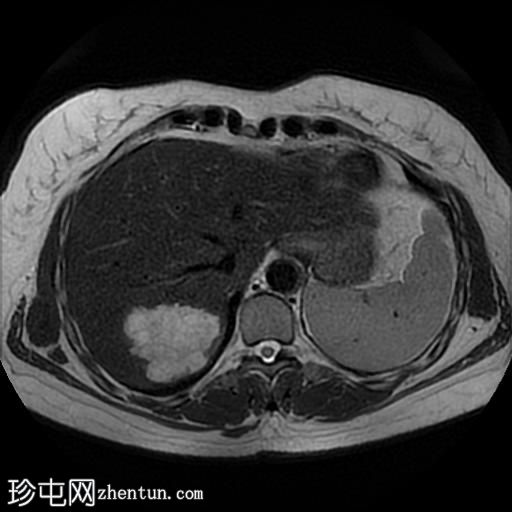

轴位T2加权像

脂肪抑制序列

肝脏第7段可见一边界清晰的分叶状肿块。T1加权像呈低信号,T2/T2脂肪抑制序列呈高信号,动脉期呈不连续结节状周边强化,门静脉期呈向心性强化,延迟期完全强化。DWI序列呈高信号,ADC值呈混合信号。